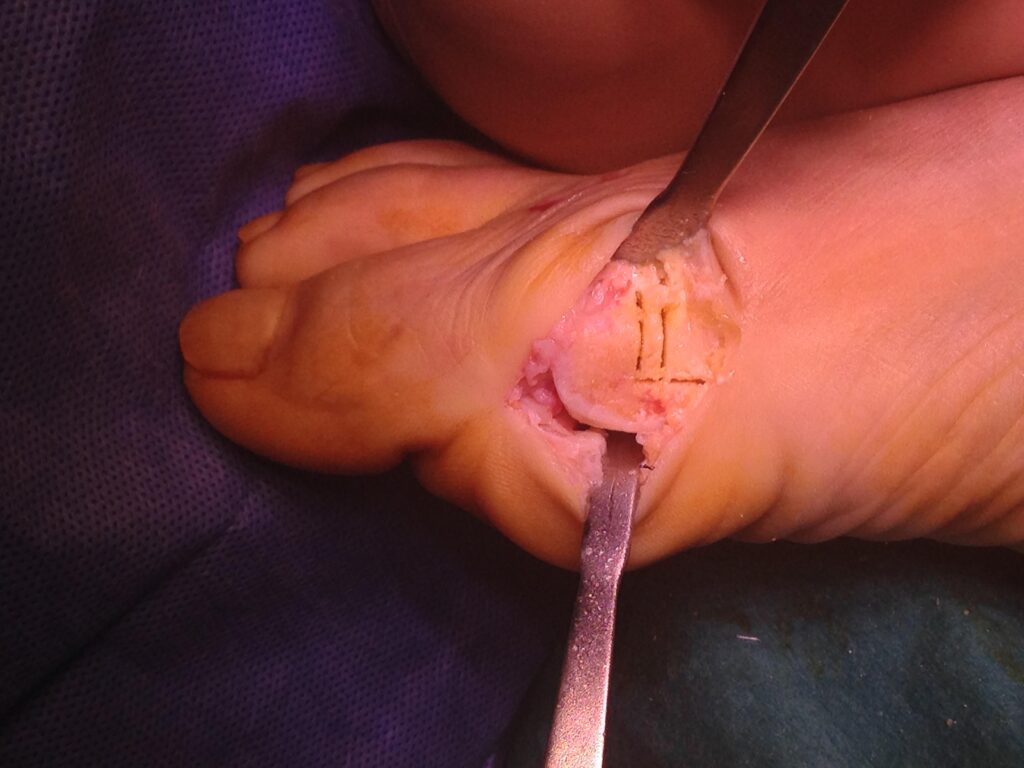

Osteotomia di sottrazione per decomprimere articolazione